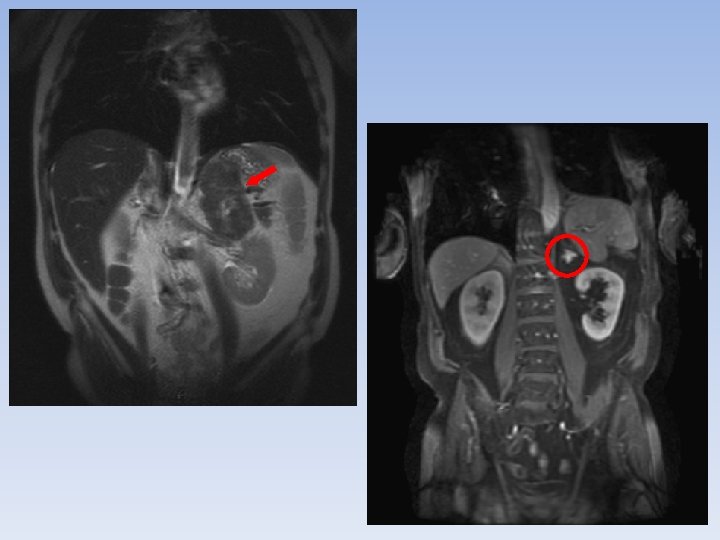

DIAGNÓSTICO TAC Tamaño: subestima. Malignidad. Crecimiento. Ø Heterogéneo. Irregular. Invasión estructuras adyacentes. Adenopatías. Distancia cortes máximo 1 cm.

DIAGNÓSTICO RMN: Sens ~ TAC Inyección de gadolinio: señal en tumores malignos. Lesiones pequeñas.